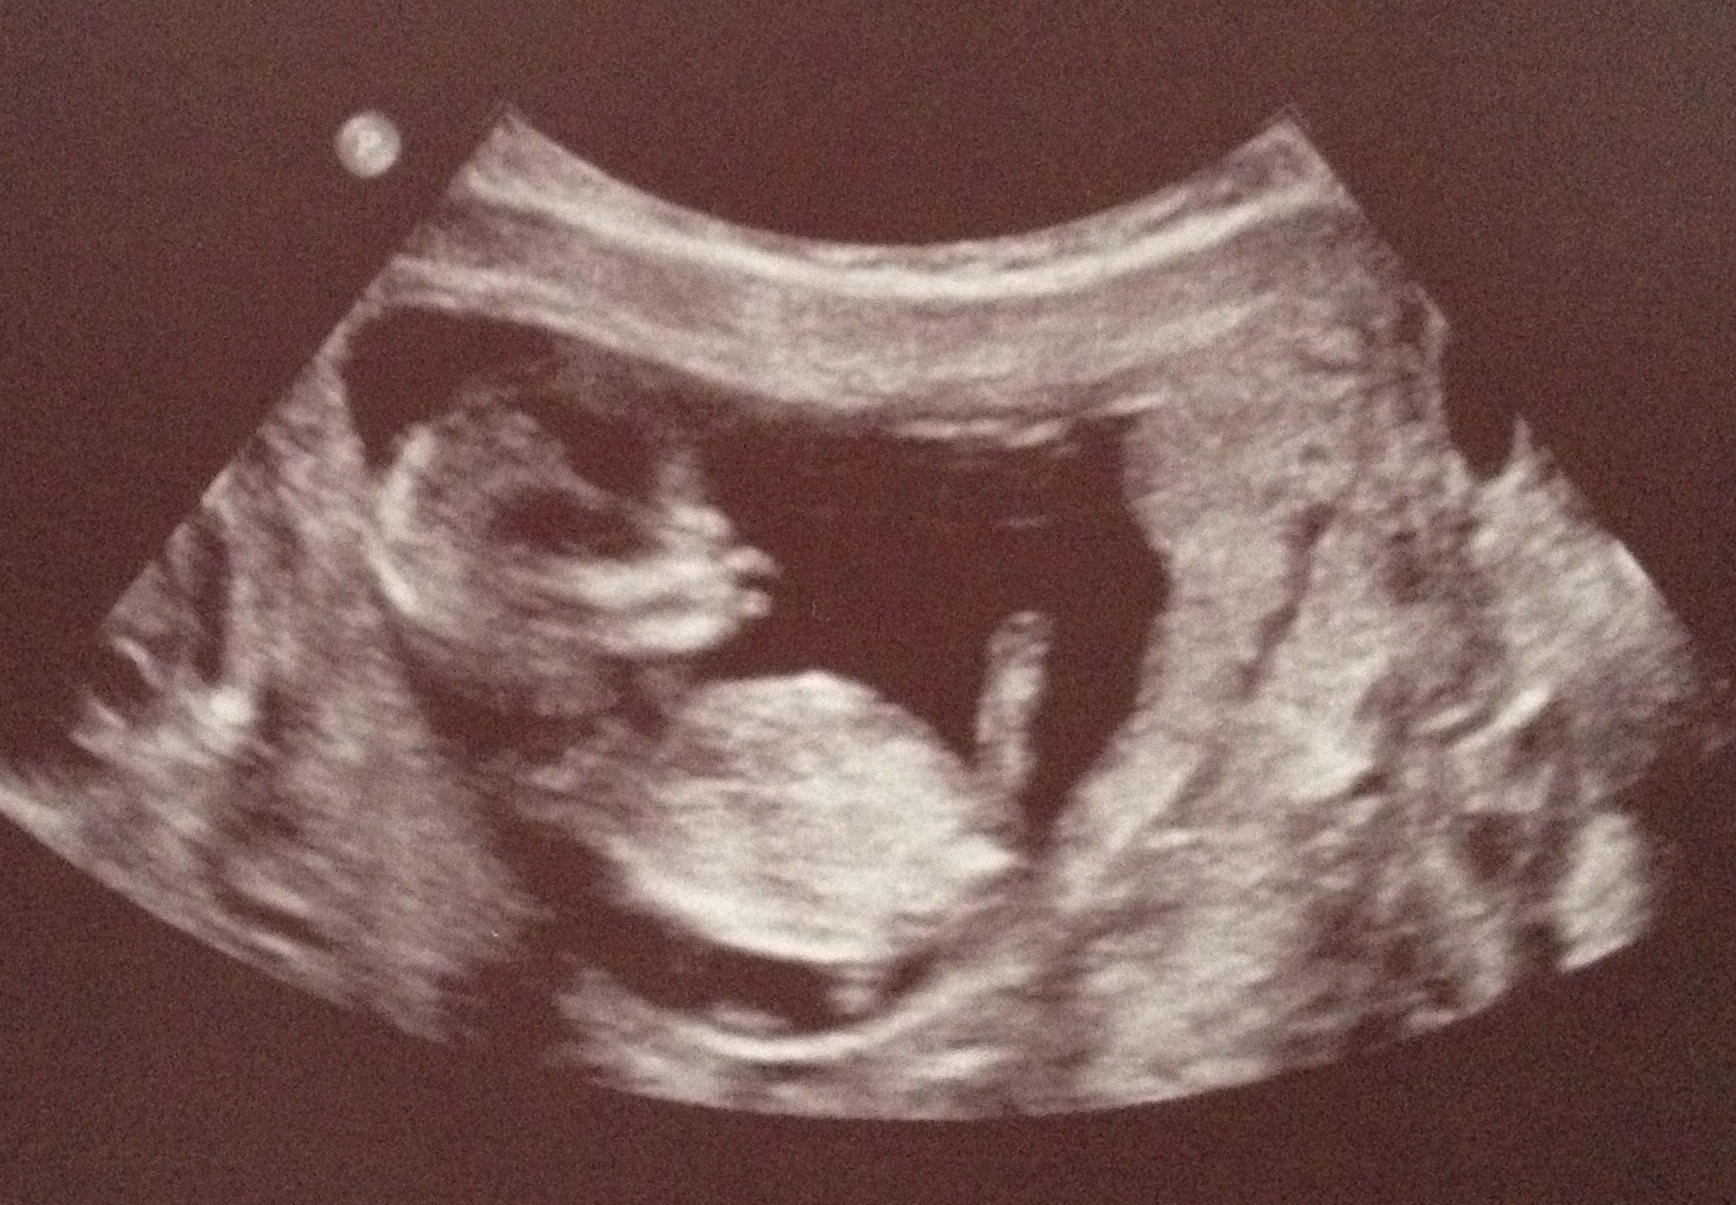

I have posted an ultrasound pic of our baby, in hopes you can provide your feedback as to what you think the gender might be based on the skull theory (boy or girl?)Attachment 19681

maybe I should have mentioned this is a 13 week ultrasound picture and I believe the nub is covered by baby's leg.